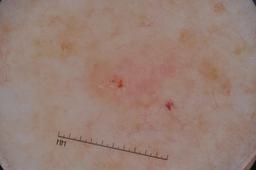

ISIC-DICM-17K (ISIC Dermoscopic Images and Clinical Metadata 17K) is a curated and balanced dataset derived from the International Skin Imaging Collaboration (ISIC) Archive Gallery. It comprises 17,060 dermoscopic images and clinical metadata (8,530 melanoma and 8,530 non-melanoma classes).

For more details, please follow the project’s GitHub repository: https://github.com/mmu-dermatology-research/isic-dicm-17k

This dataset was used in this study and benchmark to explore the effectiveness of multimodal learning for skin lesion classification:

S. Ahammed, X. Cui, W. Lu and M. H. Yap, "Skin Lesion Classification using Dermoscopic Images and Clinical Metadata: Insights from Multimodal Models," 2025 IEEE/CVF Conference on Computer Vision and Pattern Recognition Workshops (CVPRW), Nashville, TN, USA, 2025, pp. 222-230, DOI: 10.1109/CVPRW67362.2025.00027